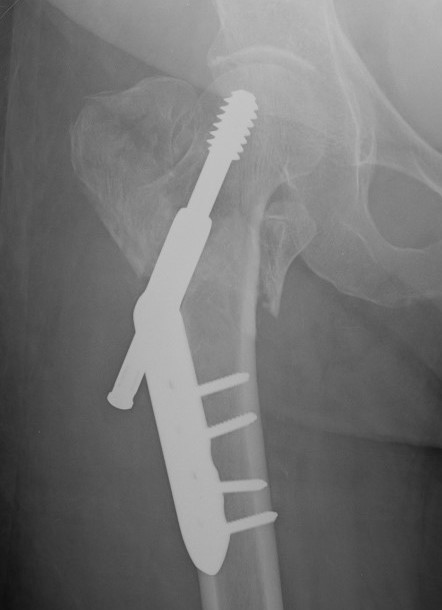

Cephalomedullary nail / Proximal femoral nail

Mechanical advantages

- load sharing rather than load bearing

- decreases lever arm

- supports medial cortex

Surgical advantages

- smaller incision / minimally invasive

- reduced blood loss

- shorter surgical times

Indications

- reverse oblique

- unstable fracture / loss of lateral buttress / loss posteromedial support

- subtrochanteric extension